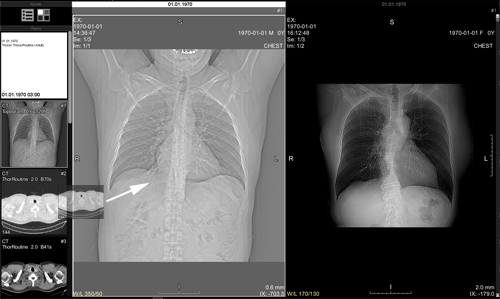

The screen will split into two parts:

The first part will contain the current study,

the second part will be about the next study in the Preview Bar

Remember to click the button again to turn off studies synchronization when you no longer need it